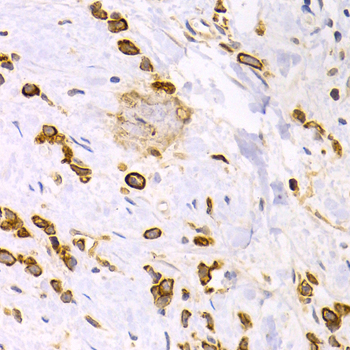

Immunohistochemistry of paraffin-embedded kidney cancer using KRT15 antibody at dilution of 1:200 (400x lens).

Immunohistochemistry of paraffin-embedded human stomach cancer using KRT15 antibody at dilution of 1:200 (400x lens).